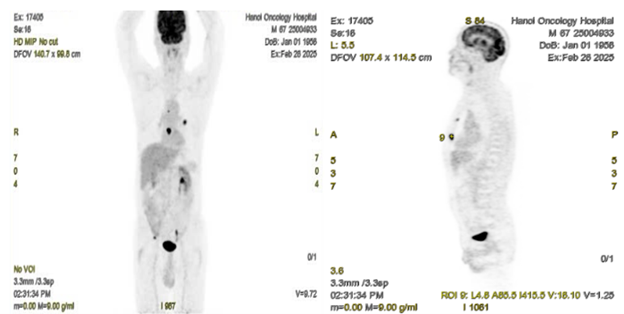

Hình 3: Hình ảnh chụp PET ở mặt phẳng coronal (bên trái) và sagittal (bên phải) thấy hình ảnh tổn thương ở phổi trái, xương ức, xương cánh chậu phải, tăng chuyển hóa FDG.